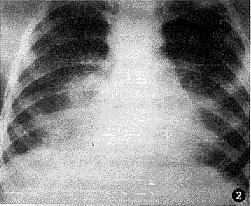

肺吸虫病[1]是由肺吸虫引起的慢性肺部感染。肺吸虫又称并殖吸虫。肺吸虫病是并殖吸虫引起的急性或慢性的地方性寄生虫病,虫体主要寄生于肺部,以咳嗽、咳棕红色痰为主要表现,也可寄生于多种组织器官,如脑、脊髓、胃肠道、腹腔和皮下组织等,产生相应症状。